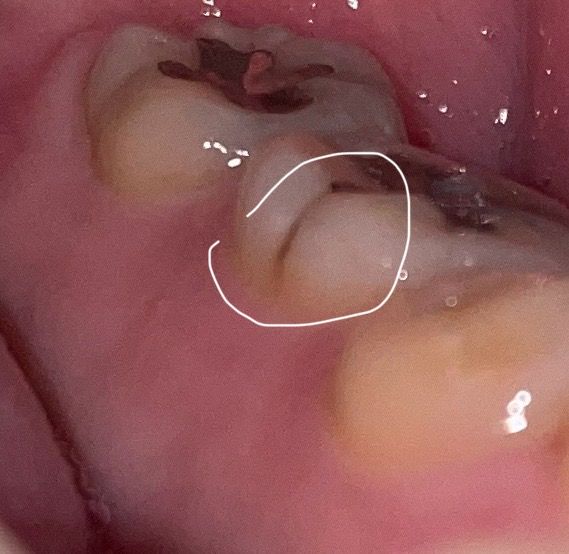

어금니에 통증이 있고 금이 간 거 같은데 치아 파절인가요?

자고 일어났을 때마다 통증이 있어서 보니까 금이 쫙 가있는데 치아가 깨진 건가요?

어떤 치료를 받아야 하나요

심하게 깨진 건가요???

• 1번 째 사진

• 현재 사진만으로 깨진것으로 보기는 어려우며, 충치가 생긴것으로도 판단됩니다. 보다 정확한 상태 확인을 위해 빠른시일내에 치과진료를 받길 권합니다.

• 안녕하세요 치과의사 김철진입니다. 엑스레이 사진을 찍어봐야 알겟지만, 씹을때 불편감이 잇다면 치아에 금이갓을 가능성이 있습니다.

• 사진으로는 정확한 확인이 힘들어 보입니다. 치아색이 변한 것으로 보여 착색이나 충치일 가능성이 높습니다. 금이 갔을 경우에도 해당 부위와 같은 검은색선을 볼 수 있습니다. 자세한 확인을 위해서 치과에서 진료를 받아보는 것을 권해드립니다.

• 해당부위는 원래 홈이 파여있긴 합니다 협면구라고 하고요

다만 사진상 보면 내부 충치가 의심되고 통증이 있다고 하니 치과를 가보시는 걸 추천드립니다